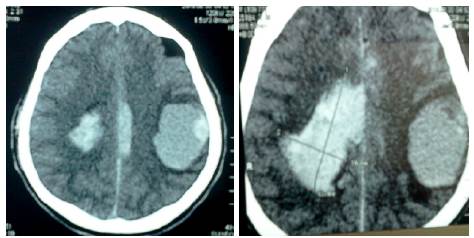

Se realizó TAC sin contraste, en donde se observó una tumoración temporoparietal izquierda, hiperdensa de 4.1x5cm, con edema perilesional y hemorragia que produce efecto expansivo severo, desviación de la línea media e invasión intraventricular (Figura 5).